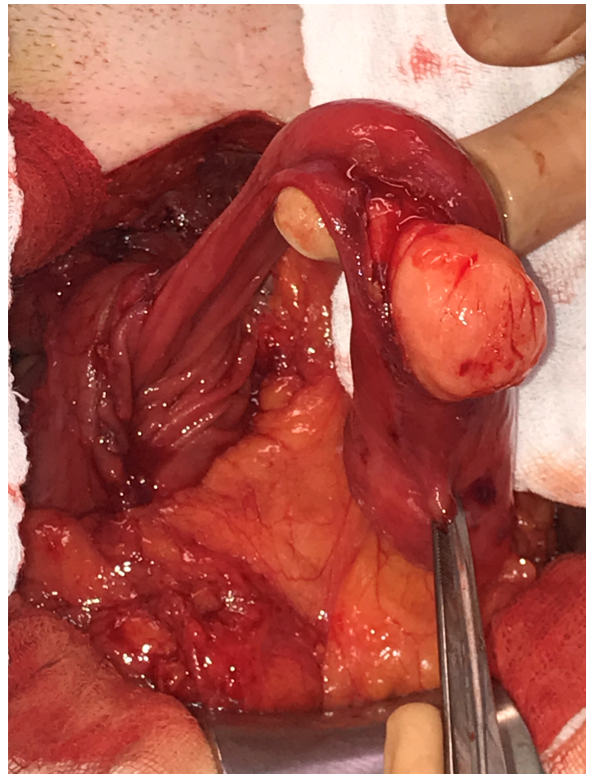

| Figure 4: Operative photo: Redo upper abdomen midline laparotomy. A longitudinal incision of the anterior aspect of the second part of the duodenum revealing a submucosal, yellowish mass originating from the posterior wall |

| Figure 5: Operative photo. Duodenal lipoma presenting itself as a large pedunculated mass, which was luxated easily through the longitudinal duodenotomy |

| Figure 6: Operative photo. The overlying normal mucosa was incised, revealing a well-defined submucosal lipoma |

Due to his surgical history, laparoscopy was not found to be a safe surgical approach. We performed a redo midline, upper abdomen, laparotomy. After extensive adhesiolysis and identification of the Treitz ligament, no mass could be palpated at this level. Proceeding with mobilization of the duodenum by performing the Kocher manoeuvre, a large mass could be palpated in the descending part of the duodenum(D2). Longitudinal duodenotomy at the level of D2 revealed a pedunculated mass originating from the posterior wall of the duodenum (Figure 4-6).

Resection was performed using a powered stapler (EchelonTM flex 60 mm), positioned at the base of the stalk of this pedunculated mass after luxating it through the duodenotomy and checking for safe distance from Vater’s ampulla. After primary transverse closure of the duodenotomy, a Blake drain was placed alongside the duodenum.